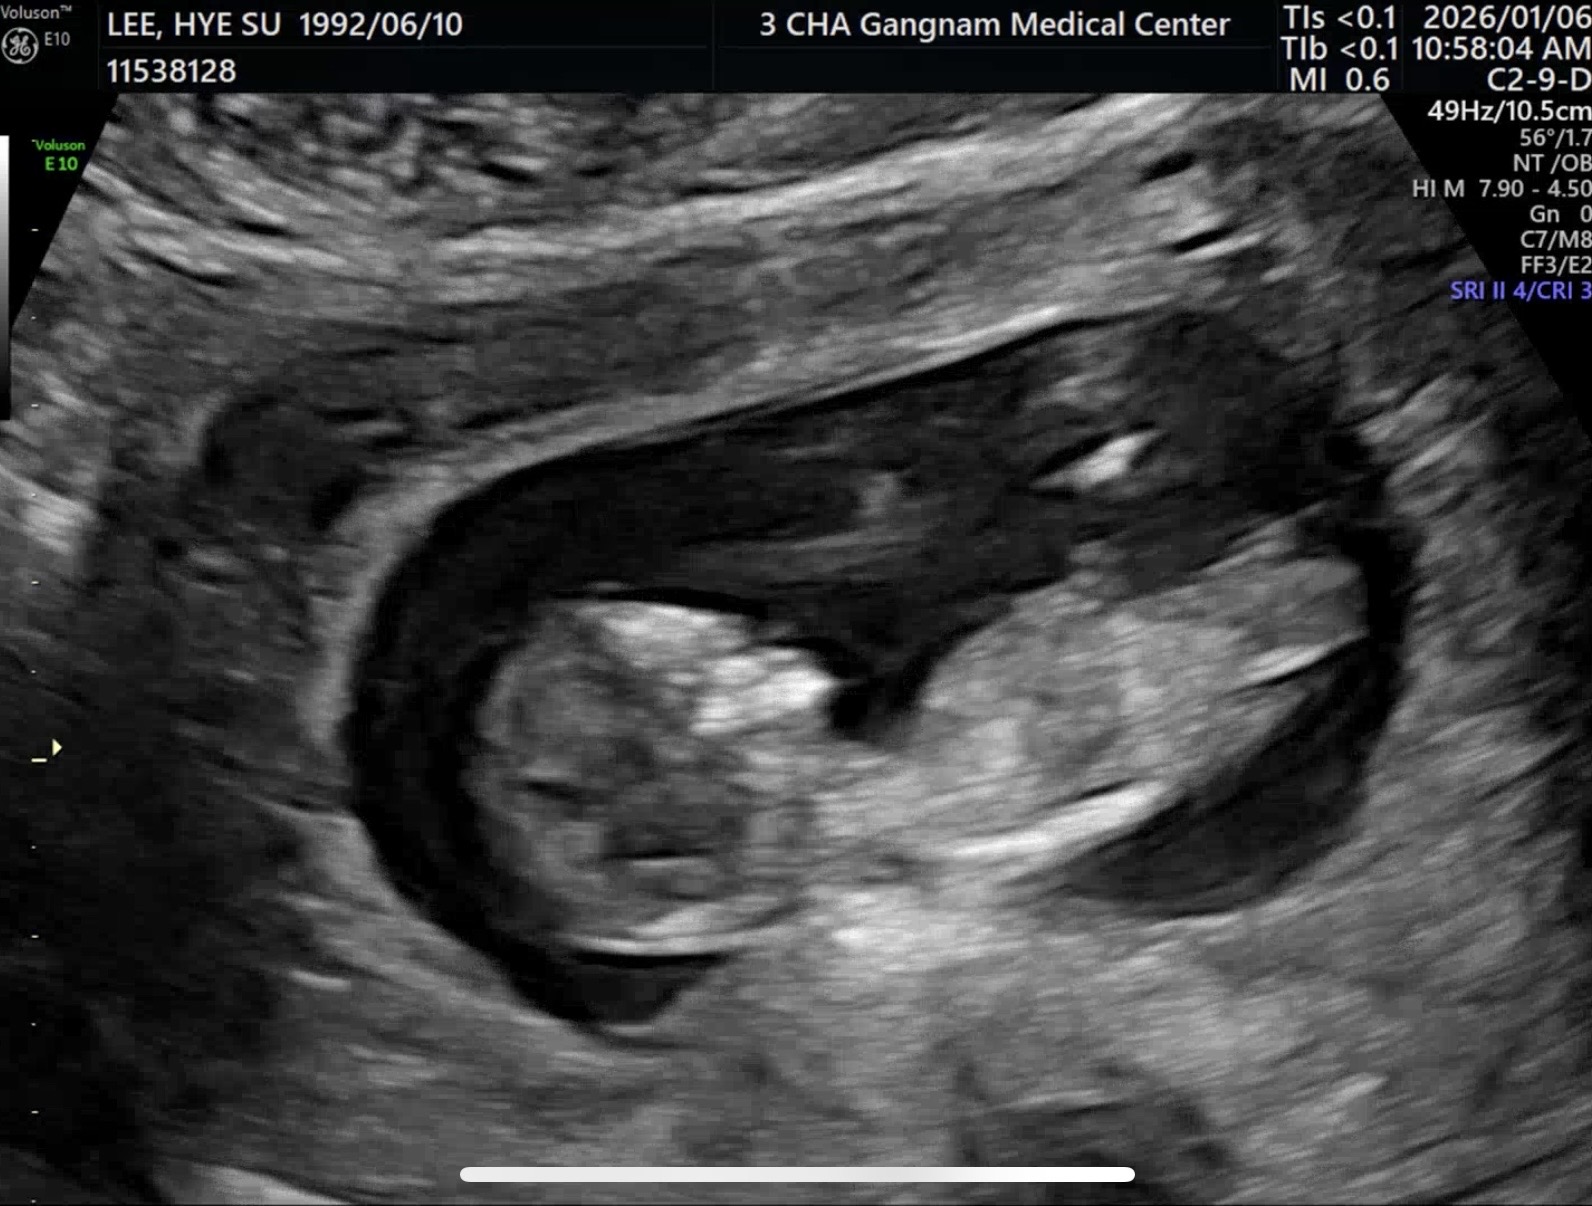

11주 5일, 1차 기형아검사하고 왔어요!! 저도 드디어 각도법을ㅎㅎ 많이 투표해주세용❤️